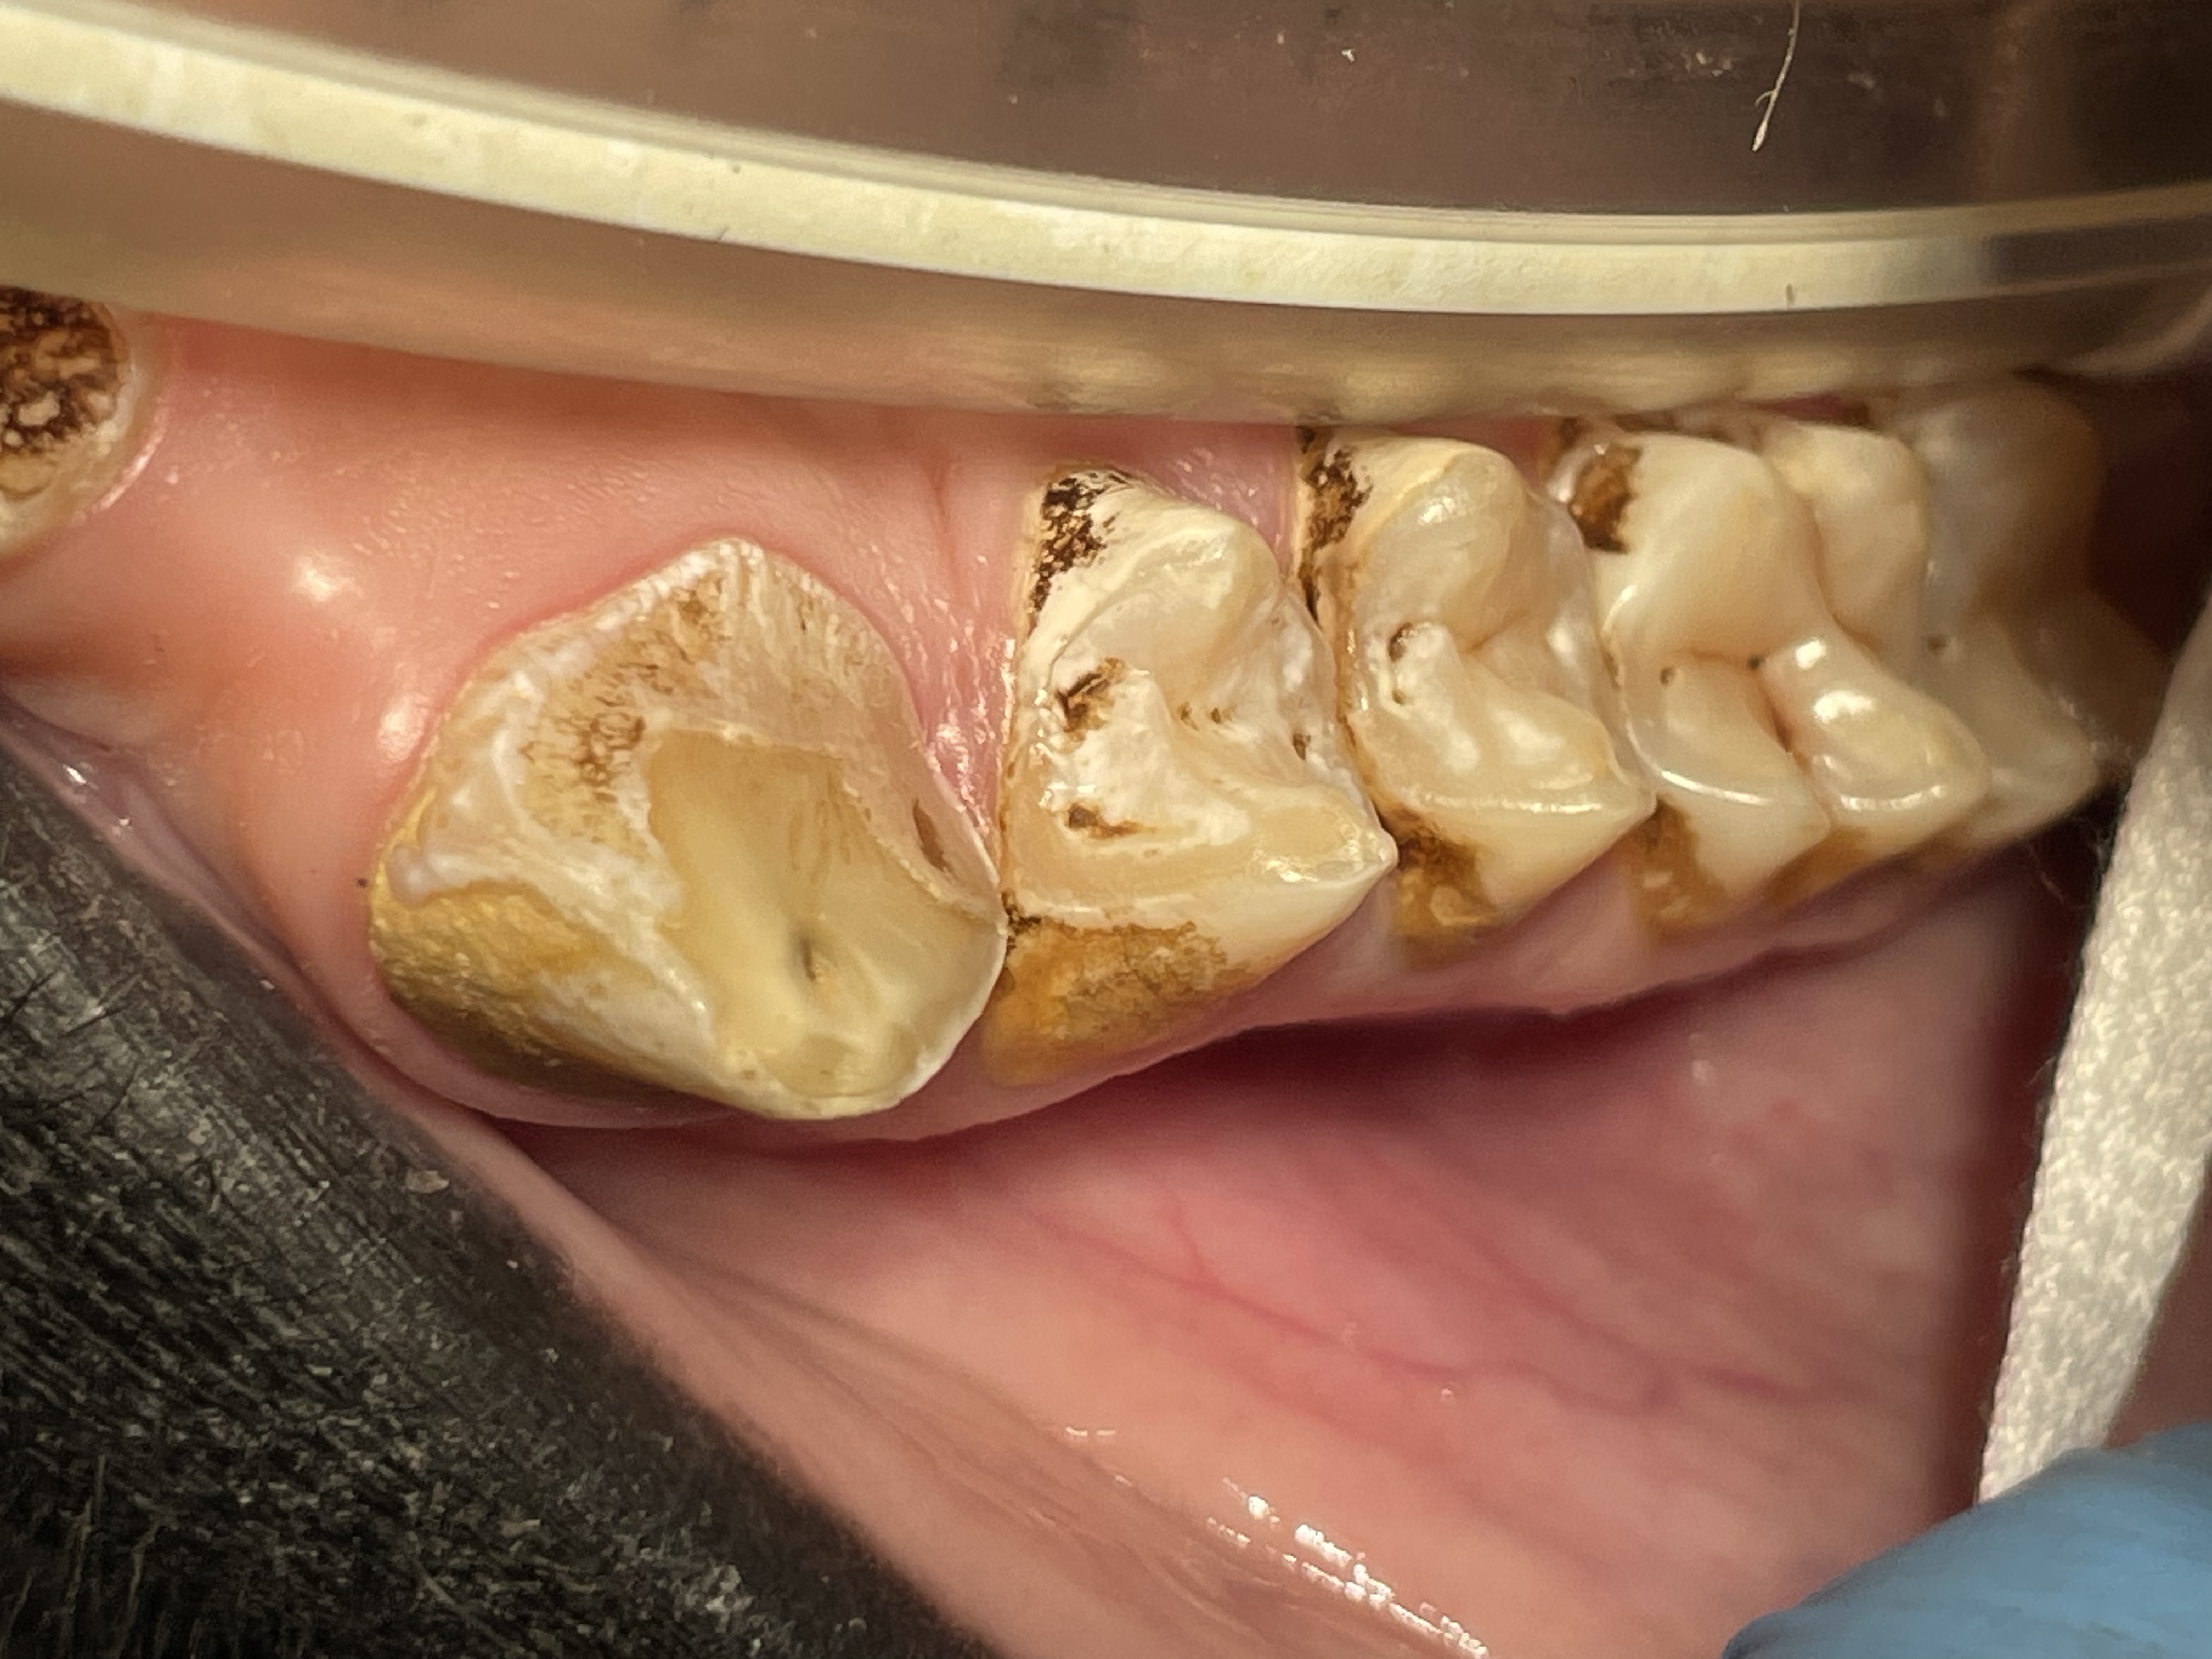

Most or our orangutans however, have had chronic, serious periodontal disease. All of our males have eventually lost all their teeth due to periodontal disease. That has not been the case with the females. We are not the only zoo that has had the chronic periodontal problems with orangutans. See Dr. Norm Stollers' paper: In the typical orangutan case that I have dealt with, there is not much accumulation of plaque or calculus. However, deep periodontal pocketing and bone loss progresses until the teeth become very mobile. I have not observed much bleeding in the most severe of these cases. We discussed preventive strategies and even tried chlorhexidine gluconate rinses to subdue the disease process. However, the orangs did not accept the products, probably due to the taste.